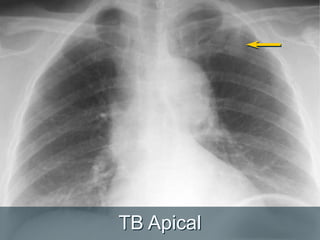

TB Apical

Faça uma segundaolhada  Ápices  Áreas retrocardiaca (esquerda e direita)  Regiões hilares  Região abaixo do diafragma